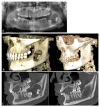

Ameloblastoma, a benign yet aggressive odontogenic tumor known for its recurrence and the severe morbidity from radical surgeries, may benefit from advancements in targeted therapy. We present a case of a 15-year-old girl with ameloblastoma successfully treated with targeted therapy and review the literature with this question: Is anti-MAPK targeted therapy safe and effective for treating ameloblastoma? This systematic review was registered in PROSPERO, adhered to PRISMA guidelines, and searched multiple databases up to December 2023, identifying 13 relevant studies out of 647 records, covering 23 patients treated with MAPK inhibitor therapies. The results were promising as nearly all patients showed a positive treatment response, with four achieving complete radiological remission and others showing substantial reductions in primary, recurrent, and metastatic ameloblastoma sizes. Side effects were mostly mild to moderate. This study presents anti-MAPK therapy as a significant shift from invasive surgical treatments, potentially enhancing life quality and clinical outcomes by offering a less invasive yet effective treatment alternative. This approach could signify a breakthrough in managing this challenging tumor, emphasizing the need for further research into molecular-targeted therapies.